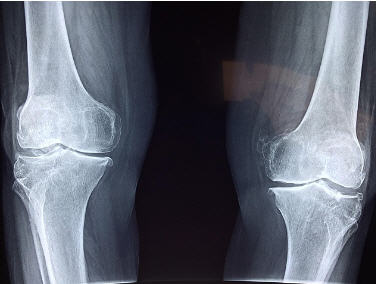

🧪 진단 방법

| 검사 종류 | 목적 |

|---|---|

| X-ray | 관절 간격 및 뼈 변화 확인 |

| MRI | 연골, 힘줄 및 인대 손상 확인 |

| 초음파 | 무릎의 수분 축적 및 염증 여부 확인 |

| 혈액 검사 | 류마티스성 질환과 다른 관절염 감별 |